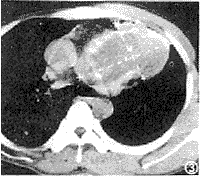

CT扫描: 左上纵隔明显宽,其内见一约10.5cm×7.5cm×8.4cm大小之密度增高块影,其内大部分呈液性密度,部分呈软组织密度,边缘处见斑片状钙化影。气管及主支气管尚通畅。纵隔内未见肿大之淋巴结(图3、4)。